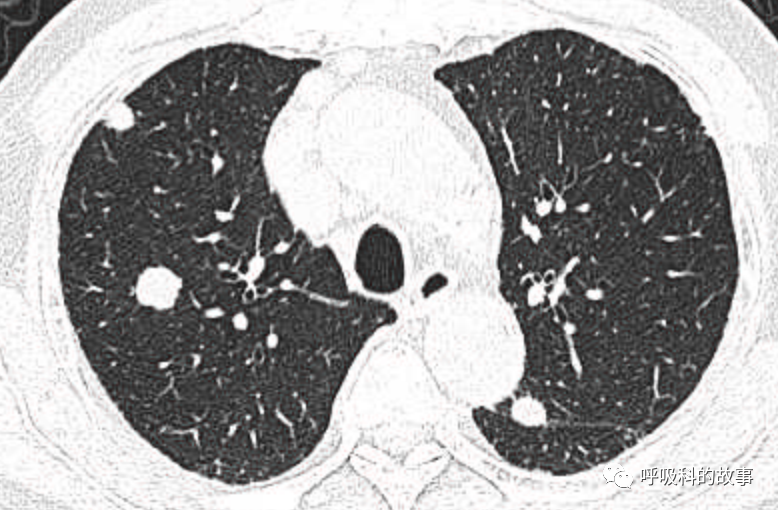

可是就在今年初,患者曾住在某院某科室,因为其他内科疾病住院。当时肺部CT也发现了在右中叶内侧段的高密度实变影,由于影像很类似肺炎,因此当成肺炎治疗。

图12-14:该患者各个角度的影像图像

(上下滑动查看全部图片)